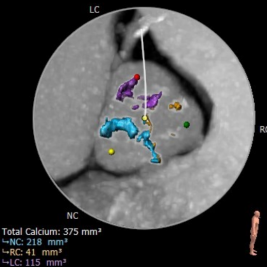

术前CT结果显示,患者主动脉瓣瓣环周长:82mm ,平均瓣环直径:26.1mm,左流出道平均直径27.0mm,瓦氏窦最小径32.5mm,窦管结合交界处(STJ)31.1mm,三叶瓣,中度钙化,钙化分布不均匀,主要位于无冠窦,瓣叶未见增生肥厚。左冠高度尚14.5,右冠高度9.9,可见右冠高度略低,结合瓣叶长度,瓣叶钙化分布等综合因素考虑,术中存在一定的冠脉遮挡风险。双侧入路血管直径尚可,无明显钙化,最小直径为8.9mm。

主动脉根部评估

冠脉阻挡风险评估及钙化程度分析